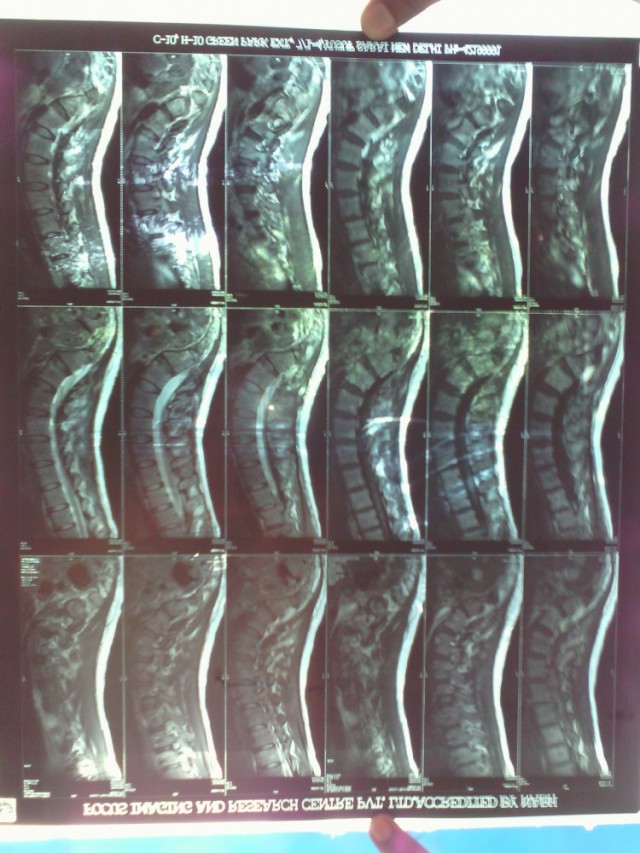

Ребята, Мира с нами, все нормально, закупили кетанов и лирику, фотки рентгена отфотографировал-сделал через прозрачное освещенное стекло-дверь, ибо оббежал Пахарганж, Коннаут Плейс, нигде не делают. Доехал до Kasturba Gandi Marg, институт Divan Chand Aggarwal Imaging Centre там отказали-слезно просил, стали звонить в институт, где эти фотки делались, сказали, что ничего не пришлют, без объяснения причин. Переговоры длились минут 20, ничего не помогло. Вот все, что удалось сделать